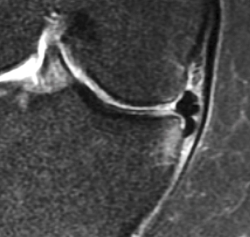

La prevalencia de lesiones meniscales (a nivel de la rodilla) en la población general –la señal intrameniscal se extiende hasta la superficie articular según la regla de los 2 cortes (Figura 3)– es la siguiente:

1. Edad 50-59 años ≈ 25%.

2. Edad 60-69 años ≈ 35%.

3. Edad 70-79 años ≈ 45%.

4. Pacientes con artrosis de rodilla ≈ 75-95%.

Figura 3. Prevalencia de lesiones y destrucción meniscales en una muestra poblacional reclutada de forma aleatoria. A: rotura del menisco; y B: destrucción meniscal no clasificada como rotura, en la rodilla derecha de una cohorte de hombres (n = 426) y mujeres (n = 565) de edades comprendidas entre los 50 y los 90 años procedentes de Framingham, Estados Unidos. El diagnóstico se basó en resonancia magnética. Los participantes no fueron seleccionados con arreglo a problemas en la rodilla u otras articulaciones. Las barras de error muestran un IC del 95% (reproducido con autorización del New Engl J Med).

Es preciso señalar que estas estimaciones no incluyen la destrucción/maceración del menisco, es decir, la ausencia de tejido meniscal normal, que también es un hallazgo frecuente, especialmente en mujeres añosas (grado B).